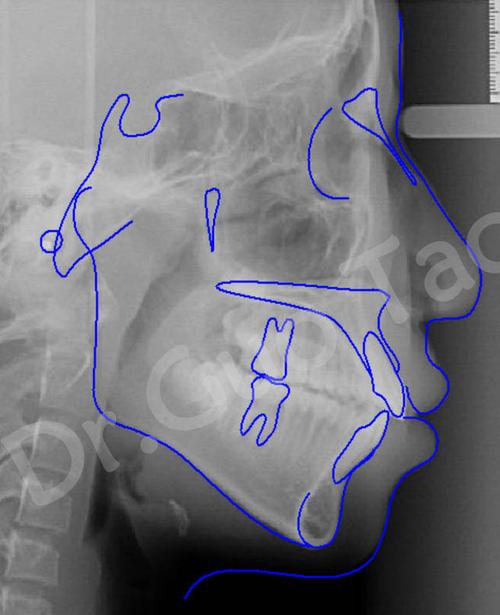

牙齿矫正头颅侧位片是正畸诊断中不可或缺的影像学检查,通过拍摄头颅侧位方向的X光片,全面评估颅颌面骨骼、牙齿及软组织的形态与位置关系,为制定个性化矫正方案提供精准依据,与普通牙片仅显示牙齿不同,头颅侧位片能捕捉从颅底到颏部的整体结构,揭示牙齿、颌骨与面部轮廓的深层关联,是正畸医生判断错颌畸形类型、预测矫正效果的核心工具。

- 图像质量控制:理想图像需清晰显示蝶鞍、鼻中隔、腭骨、颈椎等骨性标志,以及牙齿、牙根、唇部轮廓等软组织结构,无运动伪影或曝光过度/不足。